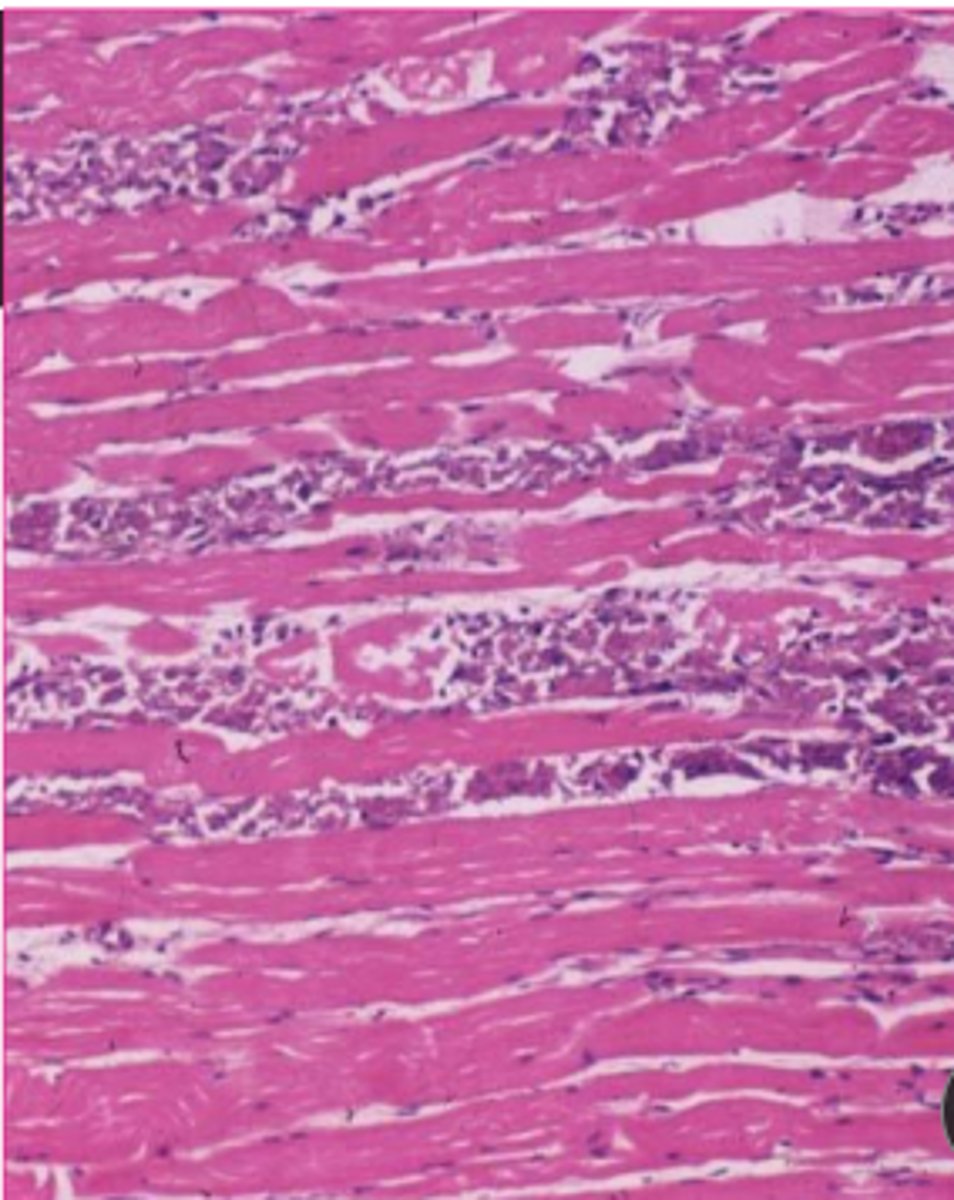

is this metastatic or dystrophic calcification?

dystrophic

<p>dystrophic</p>

what is the microscopic appearance of dystrophic calcification?

initially basophilic stippling in mitochondria which progresses to whole cell and extracellular tissue

<p>initially basophilic stippling in mitochondria which progresses to whole cell and extracellular tissue</p>